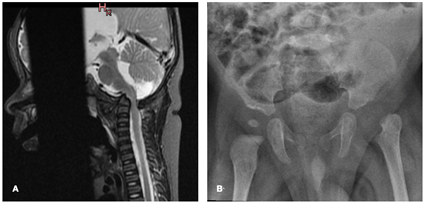

Durante dicha internación continuó con episodios de hipoventilación, destacándose los hallazgos de una nueva RNM (a los 2 meses de vida) donde se observó una alteración de las relaciones anatómicas en la región de la charnela cráneo raquídea con aplanamiento del clivus y ascenso en conjunto de C1-C2 con impacto sobre el tronco encefálico, lo cual produce la dilatación de la cisterna magna y del sistema ventricular. Así mismo, se observa proceso inflamatorio mal delimitado comprometiendo planos músculo aponeuróticos de la región cervical alta y compromiso de la masa lateral izquierda de C1 (Figura 2).

Figura 2: A, B: Corte sagital en secuencia T1 FAT-SAT (A) y T2 (B) de RNM, se observa aplanamiento del clivus y ascenso en conjunto de C1-C2 con impacto sobre el tronco encefálico, lo cual produce la dilatación de la cistarena magna y del sistema ventricular. Así mismo, se observa proceso inflamatorio mal delimitado comprometido planos músculo aponeuróticos de la región cervical alta y compromiso de C1 del lado izquierdo

En el control a los 6 meses de vida, presenta buen crecimiento y desarrollo, aunque con alguna dificultad para lograr el sostén cefálico. Del examen físico del aparato osteoarticular se destacan movimientos de flexo-extensión y rotaciones de cuello tanto activos como pasivos; mantiene la dismetría de los miembros inferiores de aproximadamente 2 cm, sin dolor a la movilización de los mismos. De la imagenología, la RNM cervical presenta recesión del proceso inflamatorio prevertebral, así como un descenso de C1-C2 sobre el tronco encefálico; mientras que en la radiografía de pelvis mantiene la luxación de la cadera izquierda con una disminución de la reacción perióstica metafisaria (Figura 5).

Figura 5: A: Corte sagital en secuencia STIR de RNM, se observa recesión del proceso inflamatorio prevertebral, asi como un descenso de C1-C2 sobre el tronco encefálico. B: Radiografía AP Pelvis, mantiene la luxación de la cadera izquierda con una disminución de la reacción perióstica metafisiaria.